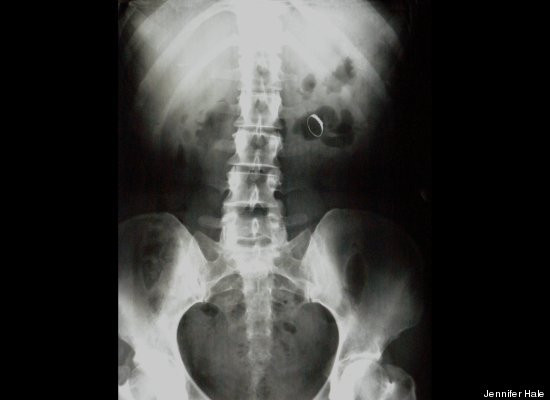

Người ta thường nghĩ chuyện đi cấp cứu do bị hóc vì vật lạ chỉ xảy ra với trẻ em, thế nhưng nhiều người lớn lại thường nuốt nhẫn cưới như một cách để giấu chúng. May mắn rằng việc này hầu như không để lại di chứng gì.